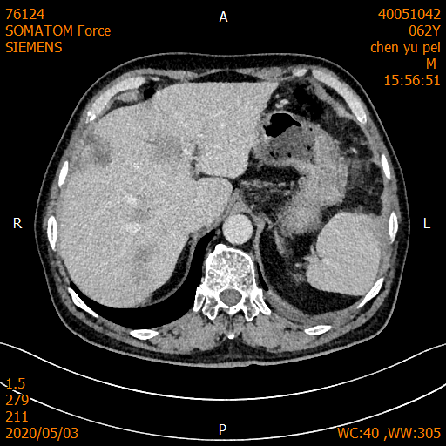

2020-02-04 CT

肝脏多发异常强化灶,考虑转移。

横结肠-降结肠交界处壁增厚强化,请结合消化道检查,腹腔部分肠管扩张积气积液,可见气液平,请结合临床。

2020-02-27 增强CT报告:

肝脏多个略低密度影,考虑转移灶,结合临床;脾脏外缘积液;

胆囊略大;前列腺钙化灶;腹腔积液;左中下腹术后改变;

腹盆腔、后腹膜多发淋巴结,局部肿大;双侧腹股沟小淋巴结。

2020-05-03 增强CT示胸部+全腹部增强CT:1、结肠癌术后:左侧腹造瘘改变,左上腹网膜增厚,请结合临床;2、肝脏多发转移,较前缩小。